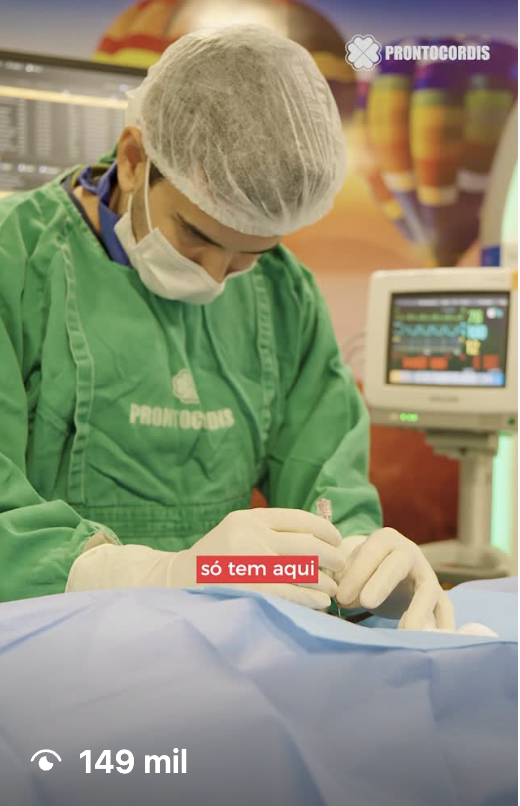

NA TOBLESS, UNIMOS MAIS DE DUAS DÉCADAS DE EXPERIÊNCIA AUDIOVISUAL, à vanguarda do marketing digital. Contamos histórias que conquistam, construímos narrativas envolventes e estratégias que conectam, convertem e entregam performance . Somos a parceira ideal para empresas e pessoas que buscam conteúdo criativo, publicidade que encanta e resultados de vendas comprovados.

Parcerias de Sucesso

A confiança de nossos clientes é a maior prova do nosso compromisso. Temos a honra de trabalhar com marcas de diversos portes e segmentos, ajudando-as a alcançar seus objetivos de comunicação e marketing.